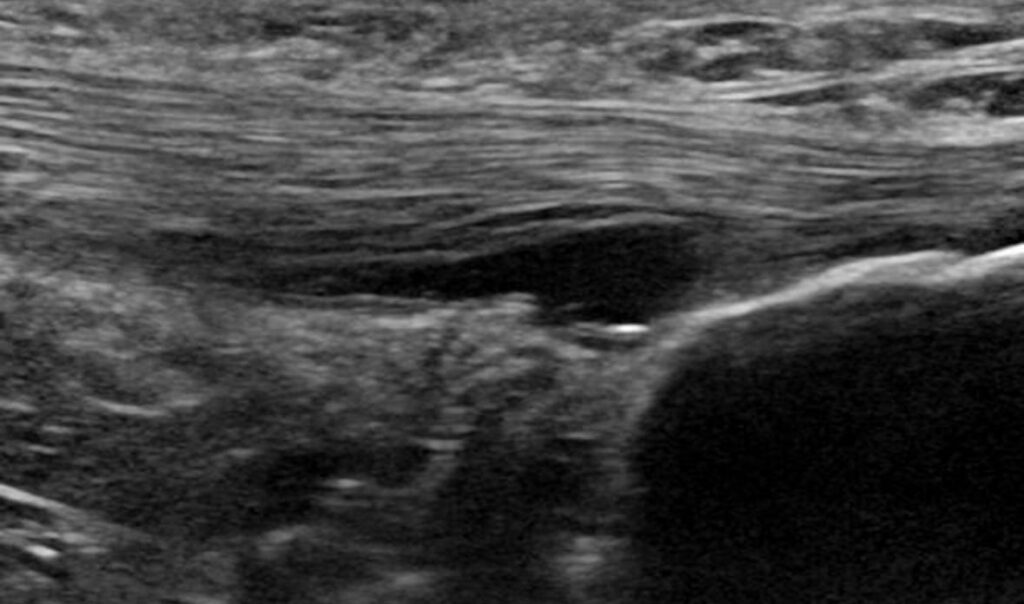

Alteración de la grasa de Kager

En esta imagen, podemos observar que el patrón fibrilar del tendón mantiene su continuidad, mantiene bien definida su delimitación a nivel profundo. Justo bajo esa delimitación, observaremos una zona anecoica en la grasa de Kager, la cual indica una desestructuración de la misma.